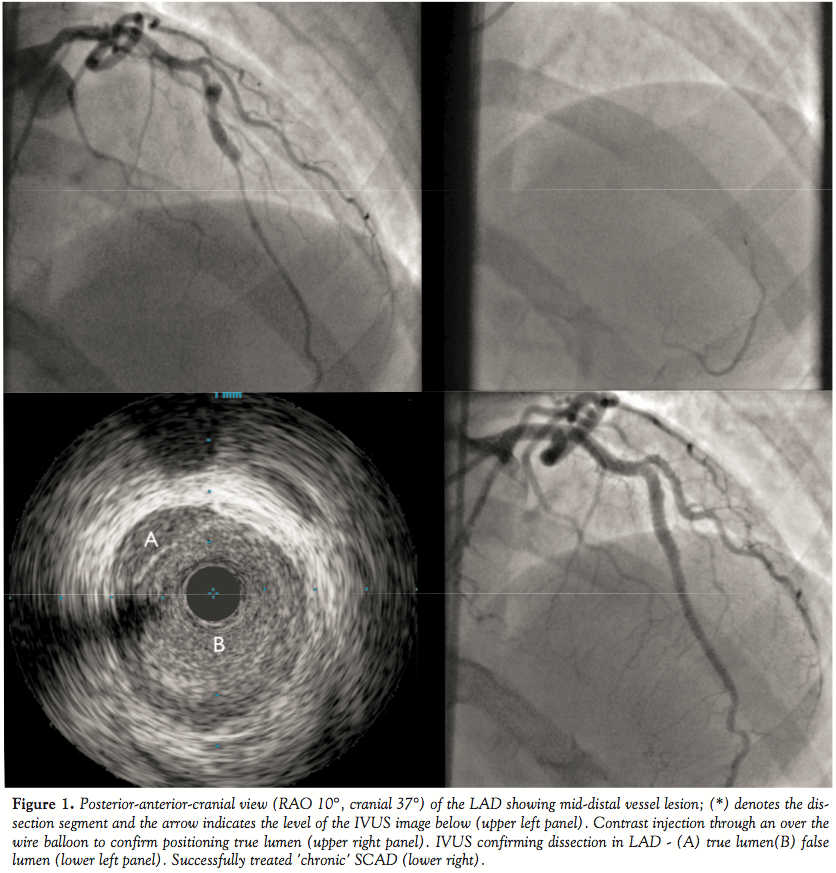

Cardiac catheterization was performed via the right femoral artery and demonstrated unobstructed left main stem (LMS), circumflex and right coronary arteries (RCA). However there was a flow-limiting lesion in the mid left anterior descending (LAD) (Figure 1). She was referred to a tertiary cardiology center for further assessment of, and possible intervention to this lesion. The patient received aspirin 300 milligrams (mg) and clopidogrel 600mg pre-loading. Further catheterization was performed via the right femoral artery using a 6 Fr sheath. The LMS was intubated using a JL 3.5 guide catheter and selective coronary angiography revealed a likely dissection flap in the mid-LAD (Figure 1). The lesion was crossed carefully with a floppy-tipped 0.016" Luge wire (Boston Scientific Corp.). To confirm position within the true lumen a Ryujin Plus over-the-wire balloon was passed distal to the lesion and injection of contrast demonstrated filling of the distal LAD (Figure 1). The dissection was confirmed on intravascular ultrasound (IVUS) using a Volcano Revolution rotational IVUS catheter (Volcano Corp.) (Figure 1). The distal end of the dissection flap was stented using a 2.75 x 28 mm Xience PRIME SV everolimus-eluting stent (Abbot Vascular), post-dilated using a 3.5 x 12mm Quantum non-compliant balloon (Boston Scientific). This was overlapped proximally with an additional 3.5 x 18mm Xience PRIME SV stent. The overlapping portion and proximal stents were post-dilated using a 4 x 12mm Quantum balloon. Full and even deployment of the stents was verified using IVUS as before, also confirming resolution of the dissection flap with a good final angiographic appearance (Figure 1). The patient was prescribed maintenance dual anti-platelet therapy of aspirin 75mg od and clopidogrel 75mg OD for a minimum of twelve months. She also received secondary prevention in the form of Atorvastatin 40mg OD and Atenolol 25mg OD.

The typical appearance of a coronary artery dissection on coronary angiography is the presence of a thin longitudinal radiolucent line representing the dissection flap with flow in two or more separate lumens.2 However, diagnosis by angiography alone is difficult: occasionally the absence of an obvious flap can lead to interpretation of the defect as a long eccentric plaque.2 Unless the appearance is very clear on conventional angiography, intra-coronary imaging with IVUS can be extremely helpful in both making the diagnosis and guiding management, as shown in this case.

There are only limited data on the optimal treatment strategy. The use of antiplatelets and heparin may limit clot/hematoma formation and its associated flow limitation.13 The mechanical effects of the compression or further extension of the dissection flap could be limited by nitrates, beta-blockade or calcium channel blockers.14 As demonstrated in our case, percutaneous coronary intervention (PCI) is possible even in long segments of established dissection. The key to PCI in these cases is ensuring that one operates within the true lumen of the vessel — in this case we utilized an over-the-wire balloon to demonstrate filling of the distal vessel with contrast injection.